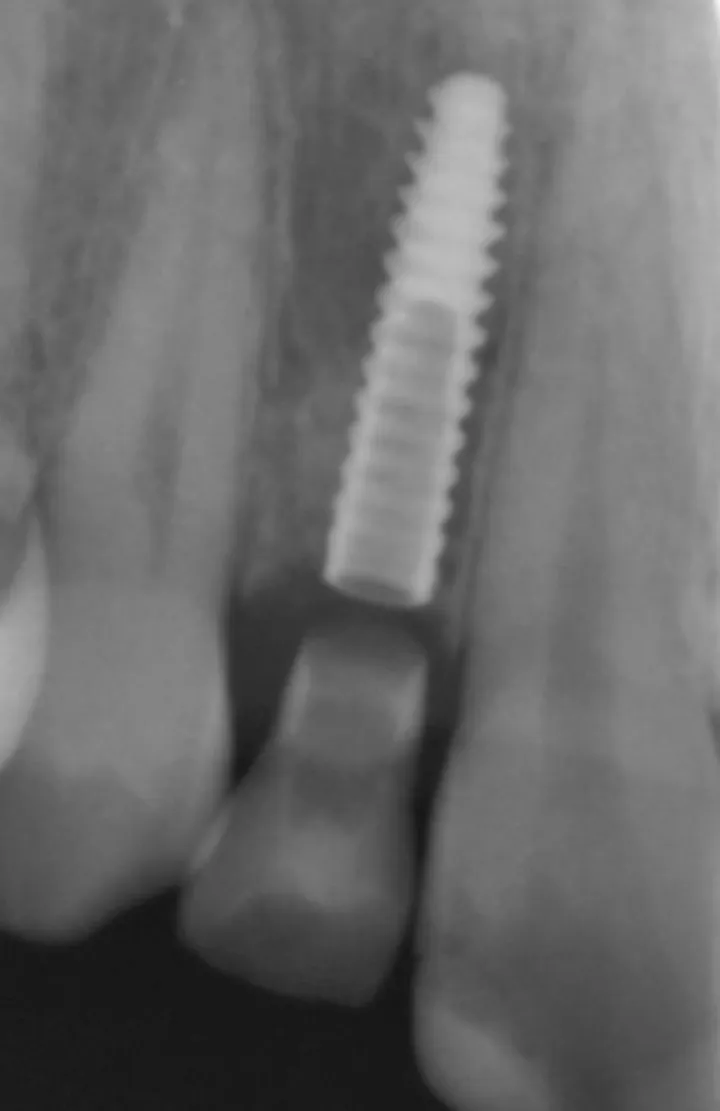

1 号病例 – Philippe RUSSE 医生(图 6 至 20)

18 岁男性患者,12、22 牙先天缺失。近远中间隙减小,种植区唇颊侧、牙槽嵴顶上方存在凹陷,适合采用小直径种植体。

图 17 :12 最终修复完成后 X 线影像。

图 18 :22 最终修复完成后 X 线影像。

图 19 :12 术后 1 年随访 X 线影像。

图 20 :22 术后 1 年随访 X 线影像。